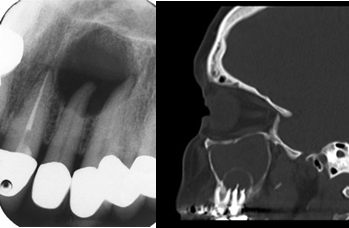

白箭头指示上颌窦牙龈瘘

根尖周炎:冷热试验; CBCT、口腔全景片PAR 或 根尖拍片OP

7、牙科常见的检查包括:CBCT(相比普通鼻窦CT能更好的显示牙齿问题,下图);口腔全景片,根尖X拍照,牙髓温度测试